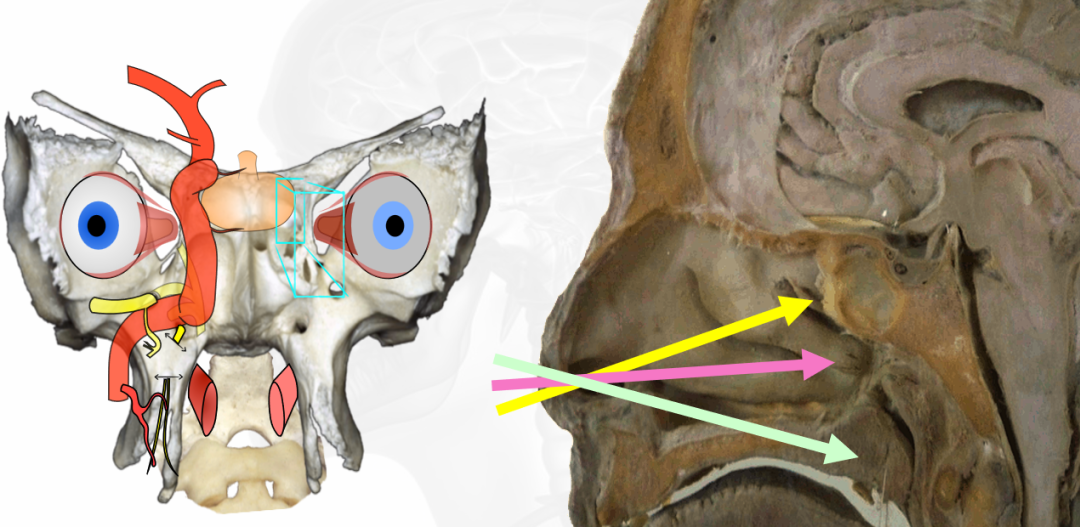

筷子技术示意图

▼单鼻孔经鼻内镜手术操作示意图